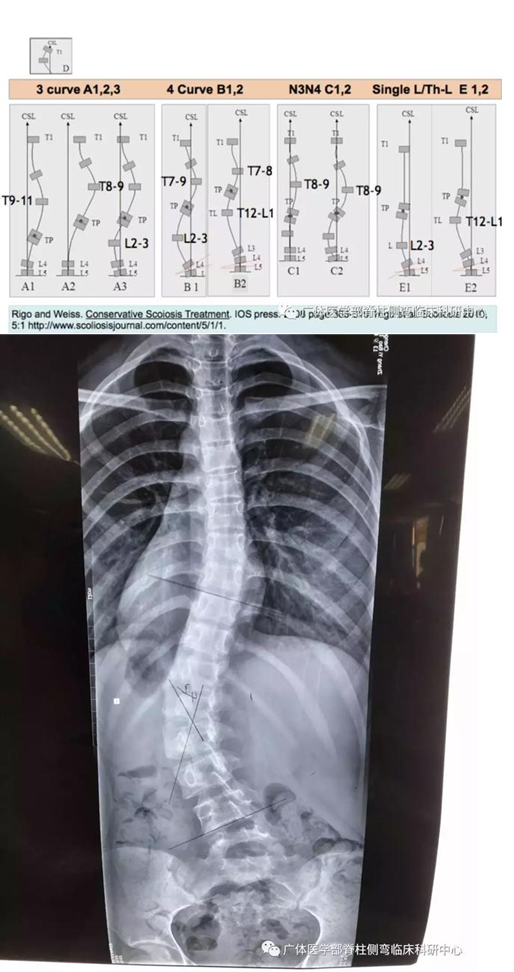

图6︰X片所示:RigoB1型,T4-T10右凸Cobb22°,T10-L4左凸Cobb42°

图7所示:自然坐姿,三维超声测量度数T4-T10右凸Scolioscan angle 20°,T10-L4左凸40°(与站立位X光片测量误差2°)

图8所示:右臀承重矫正姿势后,三维超声测量度数T4-T10右凸Scolioscan angle14°,T10-L4左凸17°